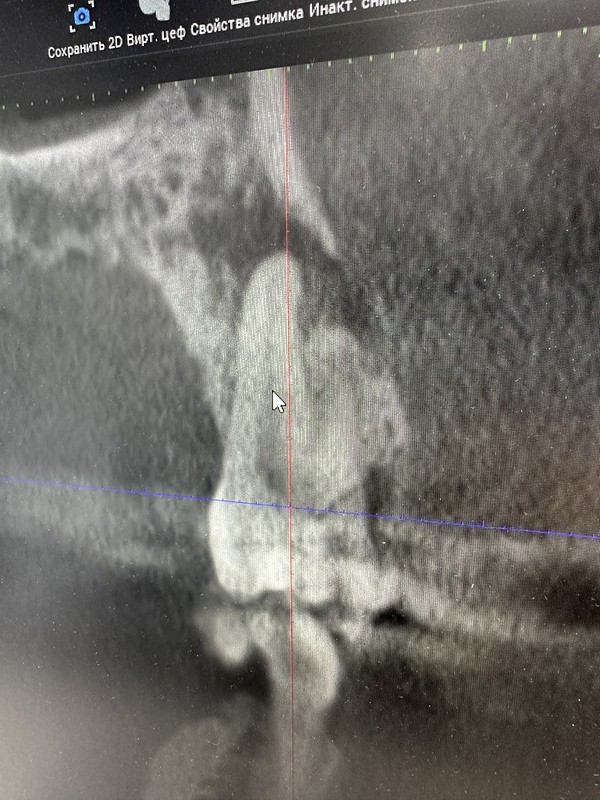

Yesterday I got a tooth pulled. I discovered a large crack in the tooth and after x-rays, the dentist needed to take it out as the root was infected. He drilled the implant base into my jaw and sewed the incision. My mouth is swollen on the left side and I have a headache today. While he was taking out the tooth, the neighboring tooth cap fell out so I am missing two teeth this weekend. I go back Tuesday to put the cap back on and take out the stitches. I always think about what people did before anesthesia and modern dental tools. Pain, pain, pain…